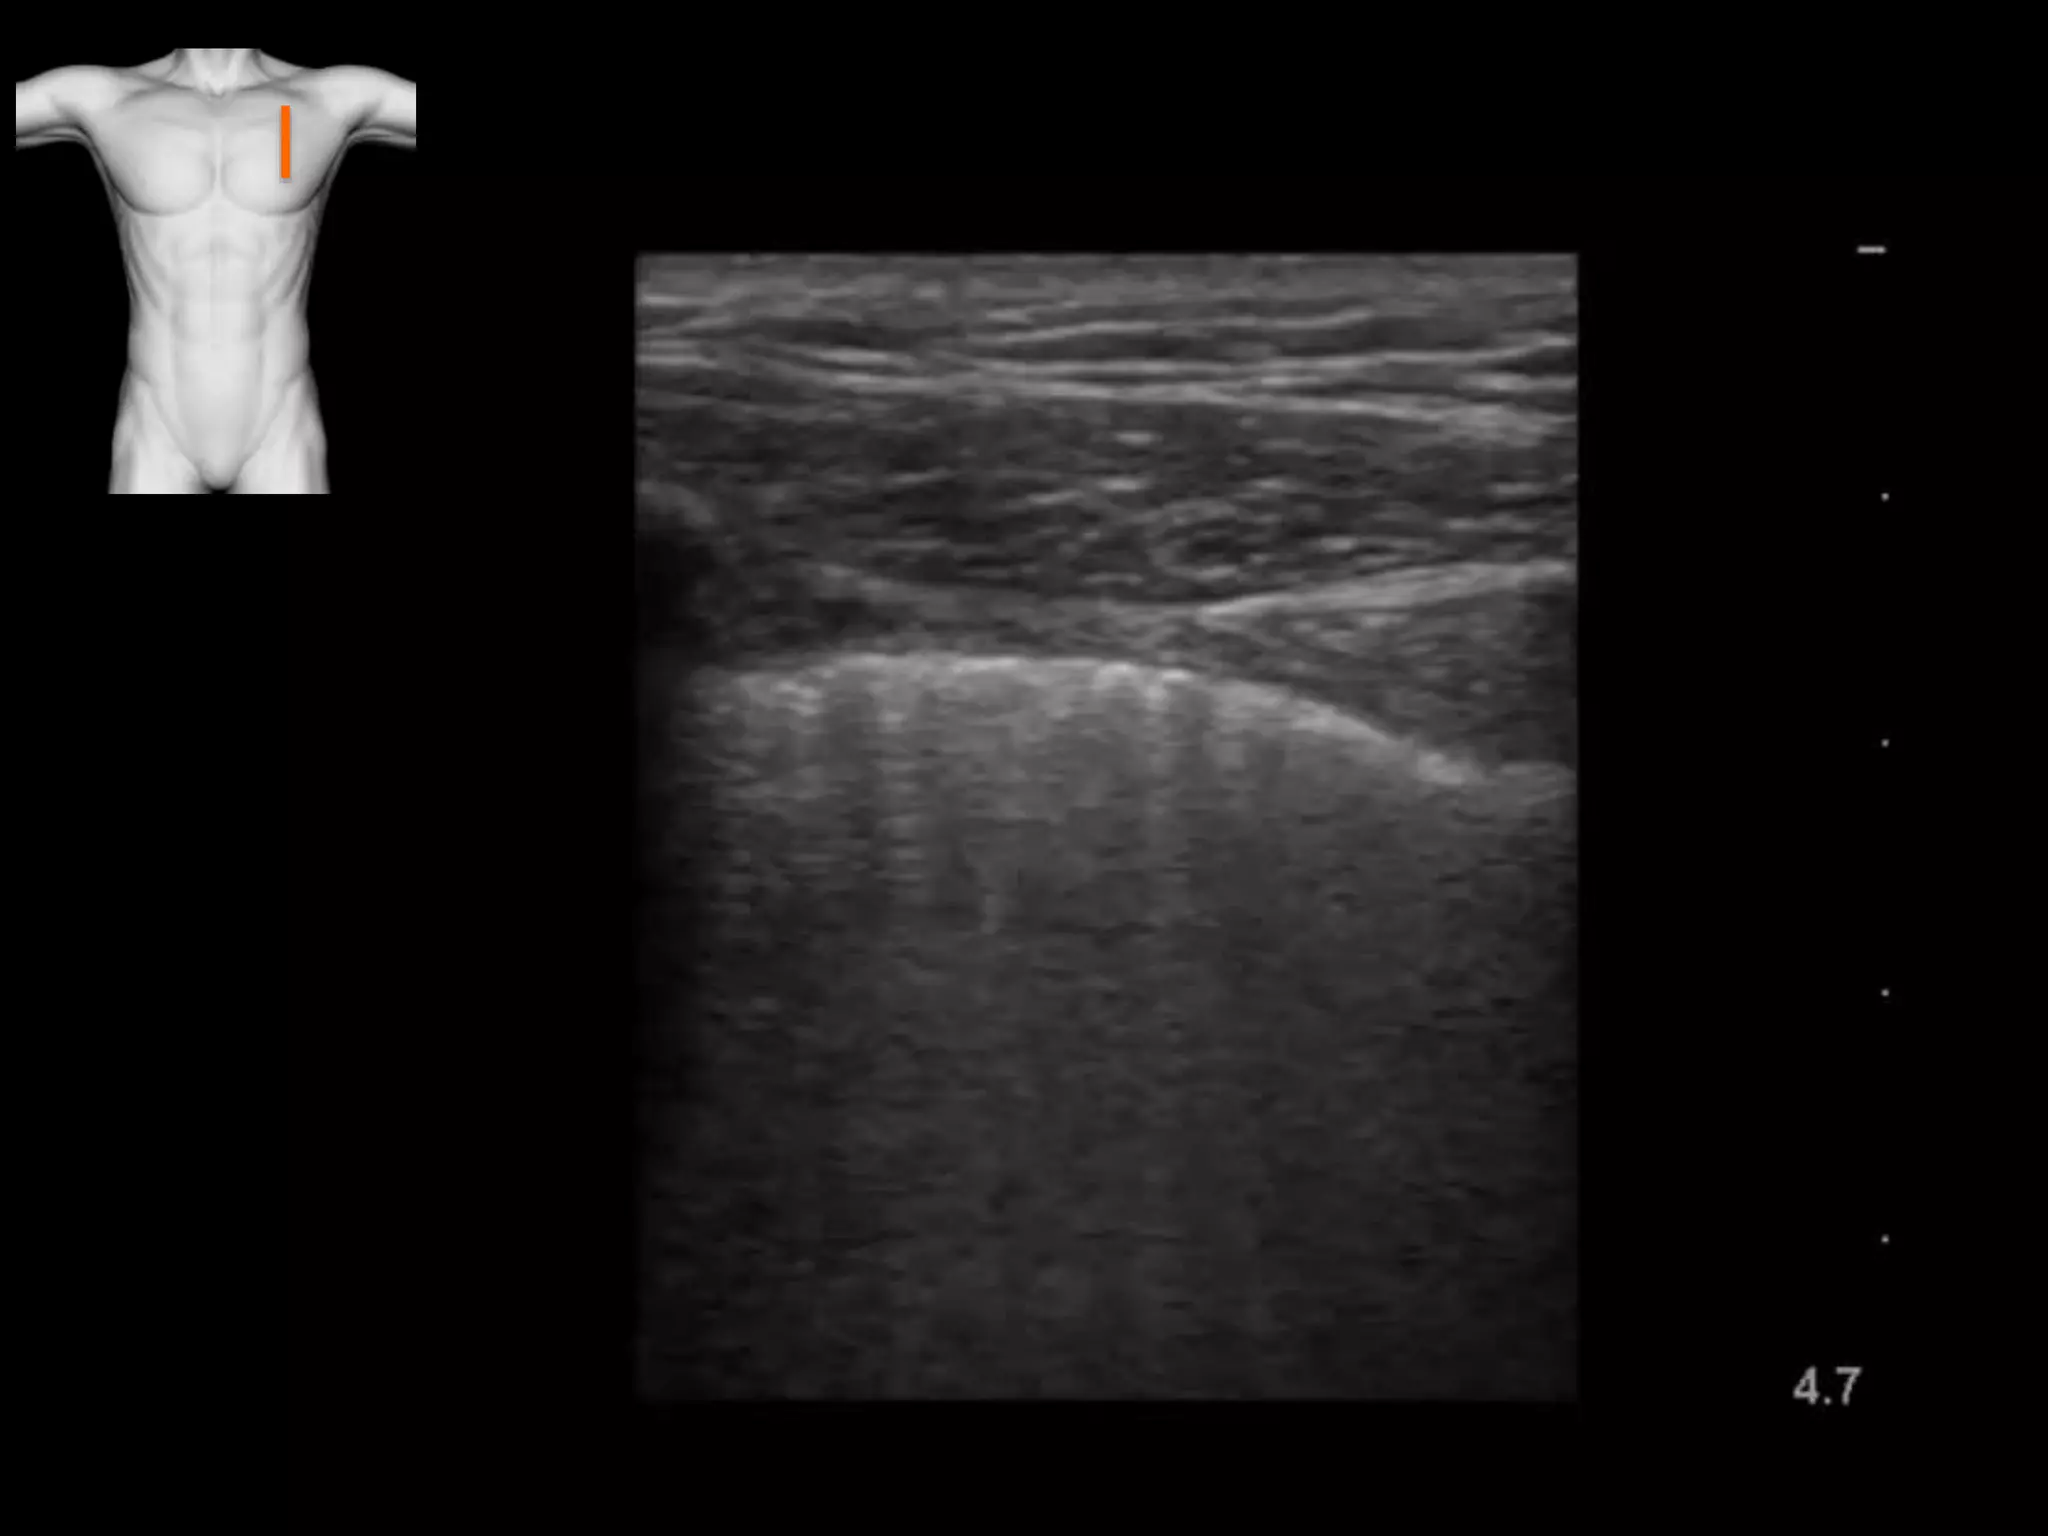

Consolidation

Solid lungs: Hepatisation, air bronchograms,

Atelectasis (compression / resorption), haemorrhage, tumour, infarction